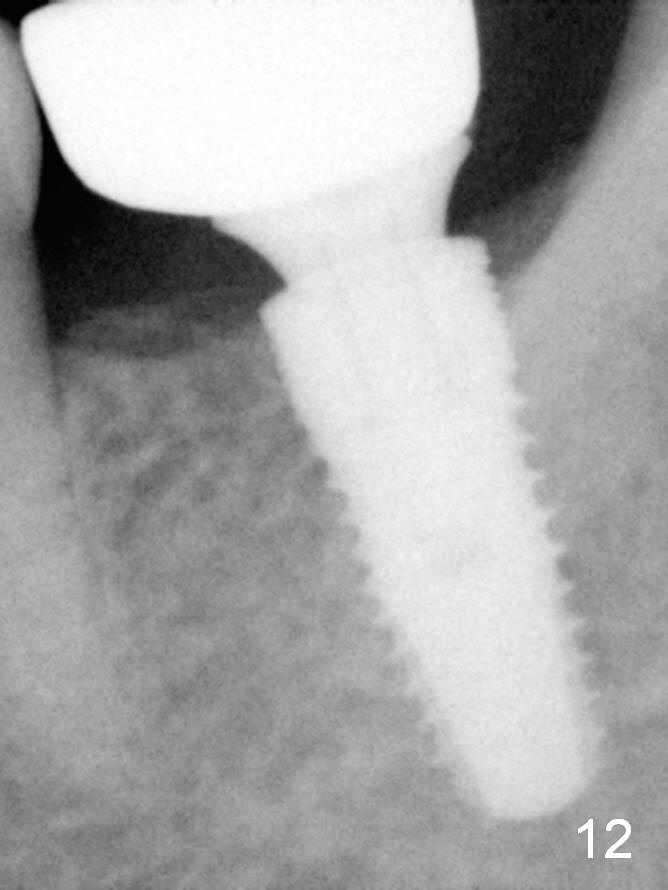

A 48-year-old lady is a dental phobic, requesting extraction of the lower left 2nd molar (Fig.1).   She returns for implant placement 9 months post extraction (Fig.2).  The ridge is mildly to moderately atrophic.  It appears that a 5x12 mm implant is appropriate for the site (Fig.3).  For safety, osteotomy is initiated at the depth of 10 mm; it appears that there is enough height for a 12 mm implant (Fig.4).  The depth is controlled by drill stopper (Fig.5 S).  Finally a 5x12 mm implant is apparently safely placed (Fig.6).  A healing abutment is placed and the incision is sutured with 4-0 Chromic gut (Fig.7).  Perio dressing is applied around the healing abutment for wound protection (Fig.8).  It appears that the healing abutment (Fig.8': *) helps stabilize the perio dressing, which remains in place 1 week postop.  When the perio dressing is removed, the wound around the healing abutment is healing (Fig.9).  There is no bone loss around the implant 3 months postop (Fig.10 (H: healing abutment), or 16 months postop (i.e., 9 months post cementation, Fig.11,12).  The patient complains of pain when she chews with the implant crown, but pain stops whenever she does not bite.  Percussion does not elicit any discomfort.  The gingiva is healthy.  There is possibility of the buccal plate being thin or the lingual plate being perforated in the submandibular fossa.  If the discomfort remains the same next 6 months, CBCT will be prescribed.